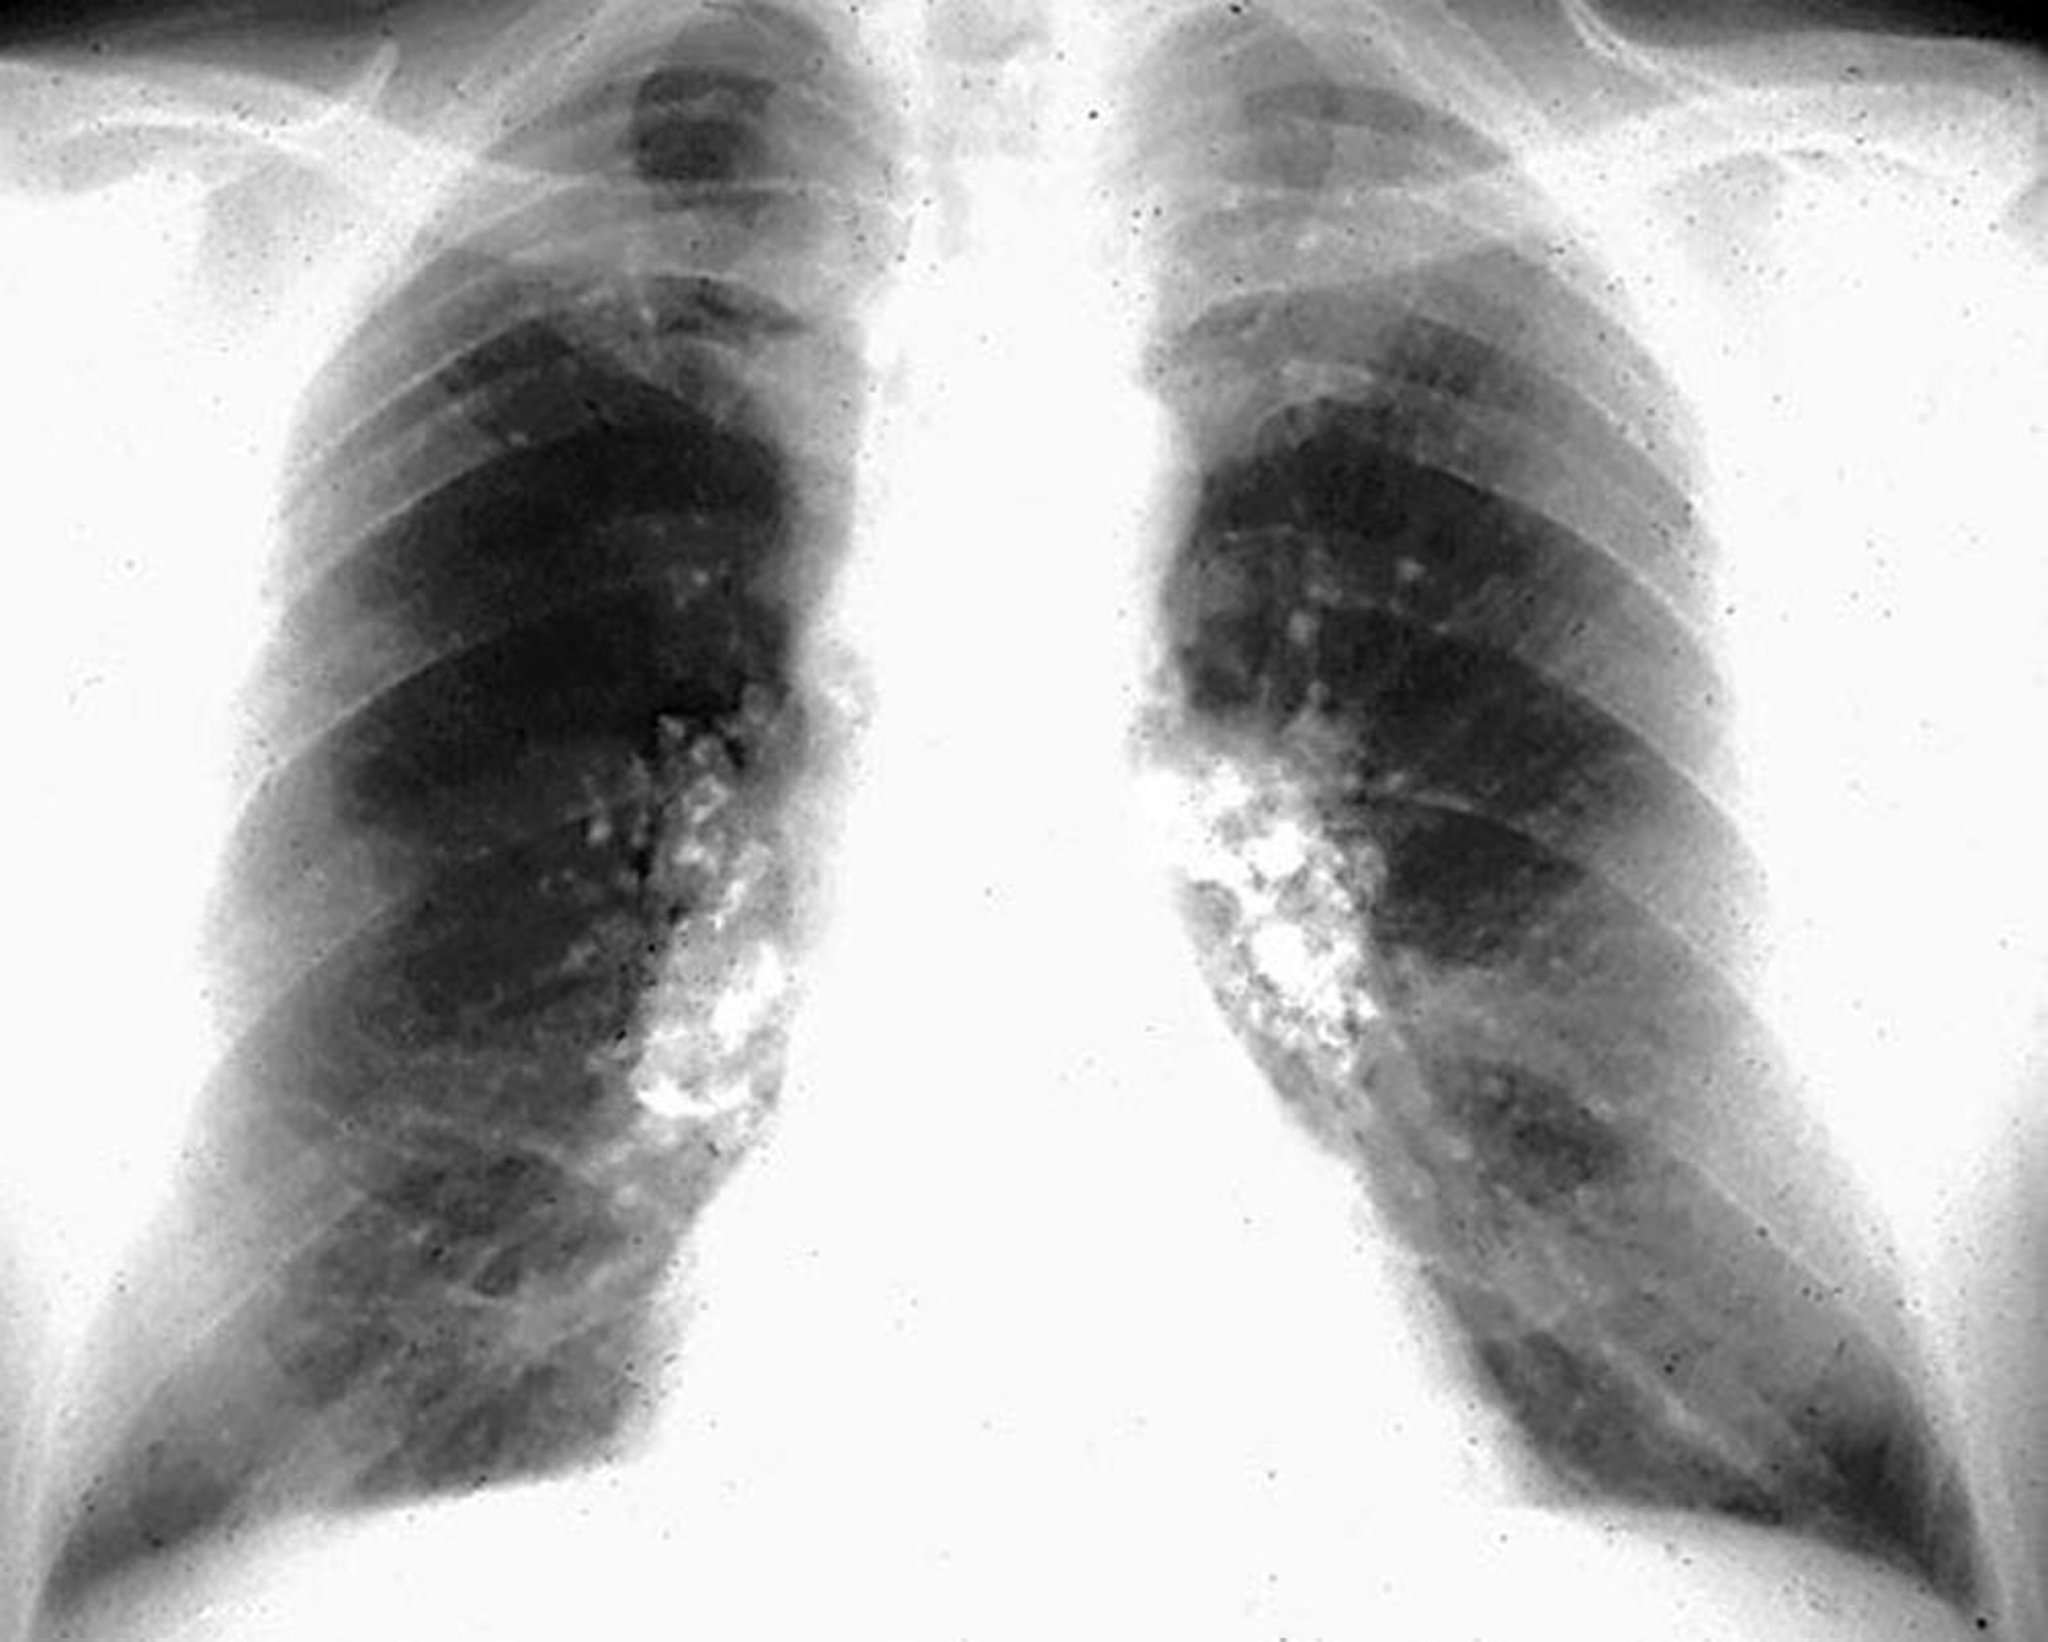

Silicose, calcifications en coquille d'œuf

Image courtoisie de David W. Cugell, MD.